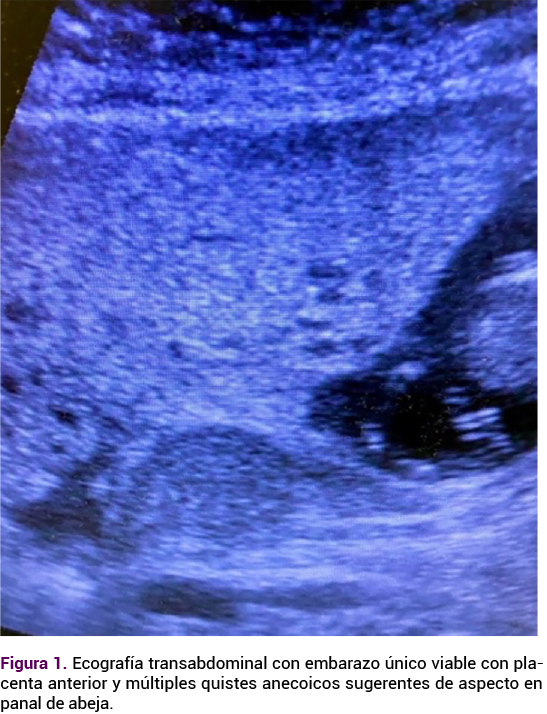

Paciente de 30 años, con antecedente de dos embarazos y una cesárea en curso de las 15 semanas de gestación, que acudió a urgencias debido a un dolor abdominal epigástrico, con náuseas y vómitos de tres días de evolución; sin control prenatal, obesidad mórbida, peso de 110 kg y altura de 1.57 m, con fondo uterino por encima de la sínfisis del pubis. La ecografía transabdominal confirmó un embarazo único viable, compatible con 14.5 semanas de gestación mediante biometría fetal, con latido fetal audible y una placenta anterior agrandada, con múltiples quistes anecoicos, de aspecto en panal de abeja y oligohidramnios. Además, múltiples quistes tecaluteínicos sugerentes de enfermedad trofoblástica compatible con mola hidatiforme parcial.

<strong>Figura 1</strong>

Figura 1.